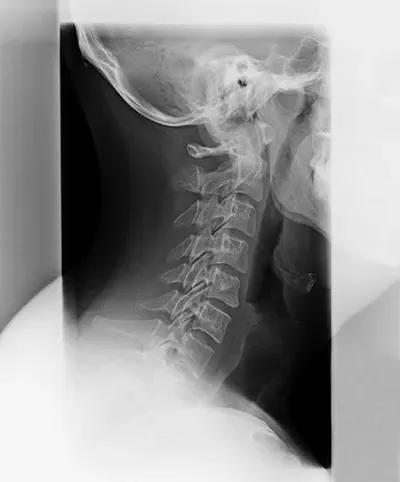

Spinal Degeneration Phase III

Phase III brings about abnormal curvature, fusing of some vertebrae, and possible permanent damage. Chiropractic care can still be incredibly beneficial as it can slow down the degeneration and remove some of the problems you’ve been having due to poor spinal health.